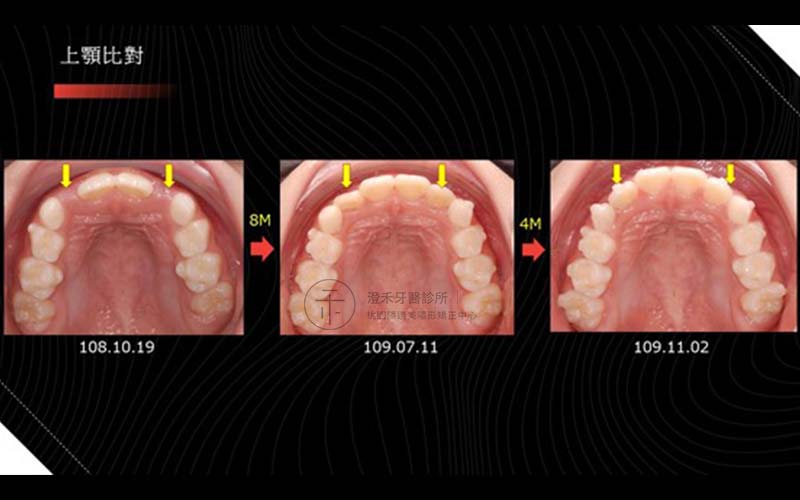

案例六

年齡:8歲

初期配戴MRC牙托,第二階段配戴隱適美矯正器,改善深咬、小下巴,以達到擴弓成果。

矯正療程:10M